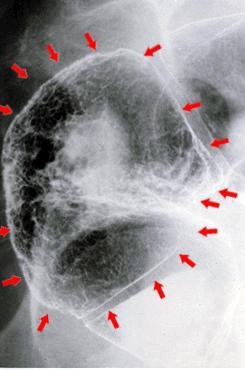

"Lesión nódulo agregante"acompañada de cáncer intramucoso en una parte, y pequeñas nodulaciones (tubuloadenomas) que se agrupan difusamente

[Image-ID:1393]

colon/recto

Rayos X

40 -

m